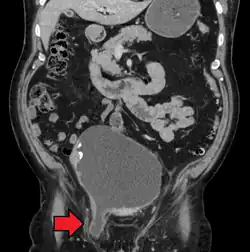

An inguinal hernia which contains part of the bladder. Bladder cancer is also present.

When assessed by ultrasound or cross sectional imaging with CT or MRI, the major differential in diagnosing indirect inguinal hernias is differentiation from spermatic cord lipomas, as both can contain only fat and extend along the inguinal canal into the scrotum.[22]

On axial CT, lipomas originate inferior or lateral to the cord, and are located inside the cremaster muscle, while inguinal hernias lie anteromedial to the cord and are not intramuscular. Large lipomas may appear nearly indistinguishable as the fat engulfs anatomic boundaries, but they do not change position with coughing or straining.[22]